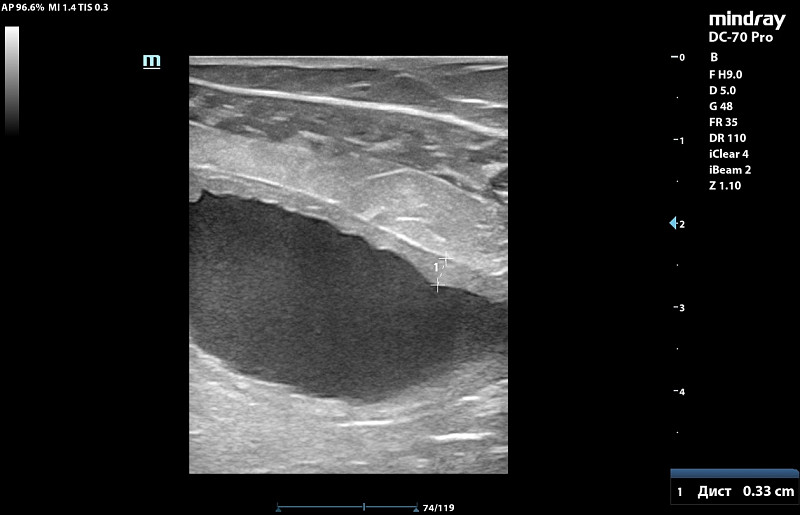

Здравствуйте! У абиссинской кошки, она астматик почти всю жизнь с дества на ингаляциях.Ей около 12 лет. На натуральном питании (бедро индейки, куринная шейка, сердечки индейки и свиной язык (только он в вареном виде, 2 года назад на таком питании все было в норме в анализах биохимияя и анализ мочи, но последние 4 мес я увеличила процент мяса в отношении, давая его 3 раза в неделю вместо языка в котором меньше фосфора)). 1.5 мес назад заметила запах у мочи и я решила подавтаь кантарен и в конце курса 8 кап на 8 кг она нагадила на пол и заметили что и запах пошел у мочи и мутная уже. Писала она 2 раза в день по многу. Крови не было. Резко стала пить больше воды по чашке дней 10 до амоксиклав. Вес не теряла ни 100 гр. Решили раз ничего серьезного подавать фураданин 1/2 таб 2 раза в день. Сильный запах почти сразу ушел. но мутность еще была, на 6 день лечения она покакала частично с поносом и тужилась и хотела остатки стула выдавить каках, стали вытирать ее и тогда словно спазм и она сделала 3 коротких метки и потом легла и пошла кровь. Крови было много, шла из мочевого канала часа три пока кошку не заперли в переноскеи в покое отсановилась уже после вет клиники. Врач хирург сказал что кажется много, а для ее веса немного крови. Ночью в ветклинике сделали узи почек и мочевого, сказали есть возврастные изменения ( они были и 5 лет назад и почки работали ок при этом), но ничего прям критичного по почкам по узи, смотреть анализы, мочевой стенка 0.3 мм вместо 0.1мм в прошлом когда кошка была 5 кг еще худее и здорова.

Сдали анализы после 8 ч голода ( не давали фурадонин 13 ч до аналиаза) Все анализы сдано 8 ч голода и 13 ч после отмены фурадонина (давали до 6 дней с пропуском 1 дозы тк 1 раз дала целую таблетку и ее вырвало. Прилагаю анализы и узи со снимками. Температуры у кошки не было, в р-не 38.1.